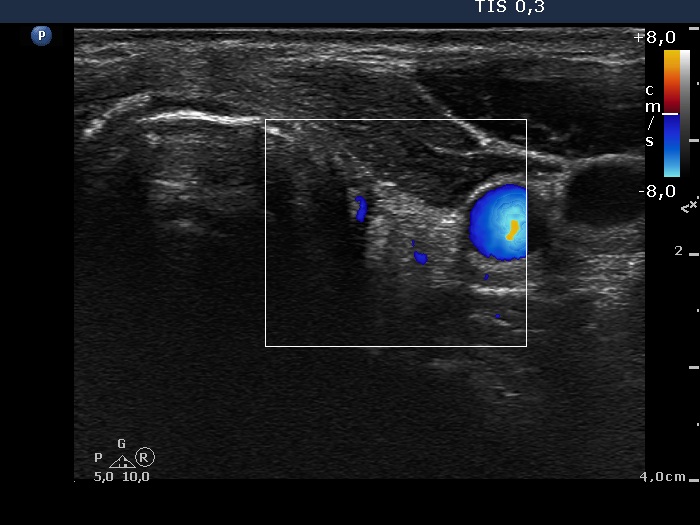

Follow-up investigation 11 months after surgery (ultrasonographic picture 6)

Left lobe, transverse scan, color Doppler mode. There is no vascularization on Doppler mode.